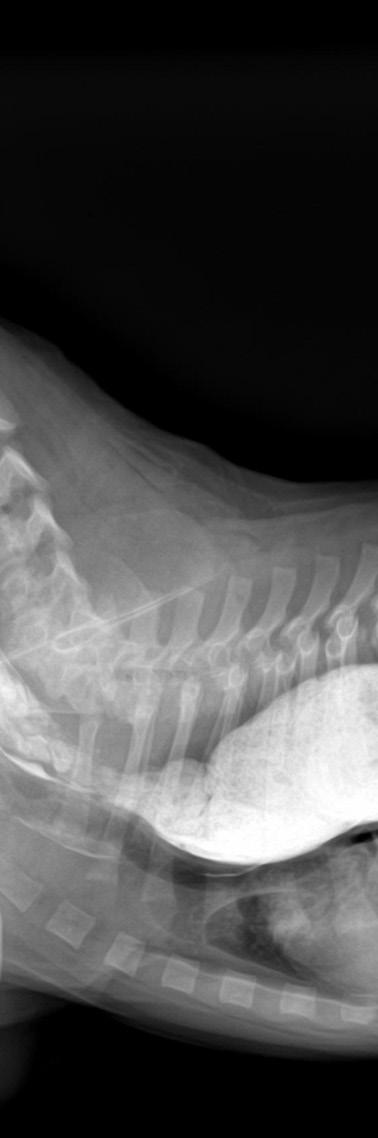

Ruby’s x-rays have been reviewed by a prominent ACVR member of my profession. We discussed the need to make sure she wasn’t an LTV (Lumbosacral Transitional Vertebrae)

dog, and it appears she is not. Her latest X-rays show the first, third and fifth coccygeal vertebrae are actually hemivertebrae creating a really uneven tailset area. An MRI might be in her future to help identify the reason for the pain and prolonged defecation, but not yet. She is a ‘high tail kink’ dog at this time. Kinked tails are supposed to be innocuous. But, that is not the case here. Her pain is real. My family and I will care for her and offer her a performance life as part of our pack. We lovingly call her “Aunt Ruby” already. She has had chiropractic work done and has had sporadic doses of anti-inflammatory medication if she is hurting.